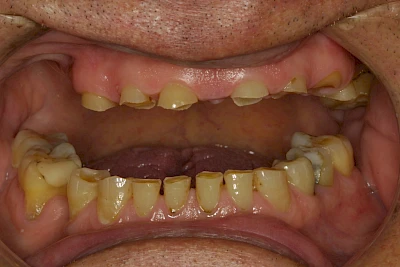

Über die Zeit können verschiedene Prozesse die Zahnhartsubstanzen aufzehren:

- Abnutzung durch Kauen (Abrasion) oder duch durch übermäßiges Knirschen bzw. Pressen (Attrition)

- Säurebedingte Auswaschung (Erosion)

- Knirschen bzw. Pressen und ungünstige Putztechnik (Druck): keilförmige Defekte

Die Zähne können dabei auf Reize (warm, kalt, süß, sauer) oder auch beim Zähneputzen empfindlich oder schmerzhaft sein. In allen diesen Fällen ist es sinnvoll, den Zahnarzt zu kontaktieren und das weitere Vorgehen abzustimmen.